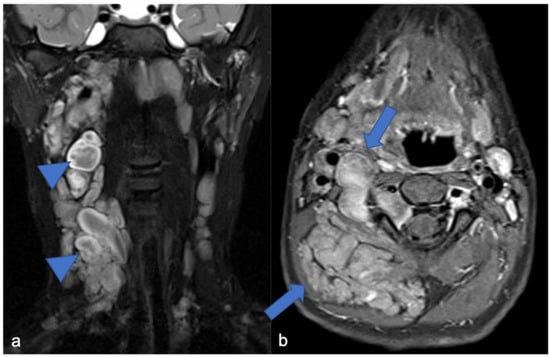

- Andersson, C.; Österlundh, G.; Enlund, F.; Kindblom, L.-G.; Hansson, M. Primary spinal intradural mesenchymal chondrosarcoma with detection of fusion gene HEY1-NCOA2: A paediatric case report and review of the literature. Oncol. Lett. 2014, 8, 1608–1612. [Google Scholar] [CrossRef] [PubMed]

- Di Giannatale, A.; Colletti, M.; Russo, I.; Ferruzzi, V.; Anna, V.A.D.; Cozza, R.; Colafati, G.S.; Messina, R.; Mastronuzzi, A.; De Vito, R.; et al. Intraspinal Mesenchymal chondrosarcoma: Report of a Pediatric case and literature review. Tumori 2017, 103, S66–S72. [Google Scholar] [CrossRef]

- Wang, L.; Motoi, T.; Khanin, R.; Olshen, A.; Mertens, F.; Bridge, J.; Dal Cin, P.; Antonescu, C.R.; Singer, S.; Hameed, M.; et al. Identification of a novel, recurrent HEY1-NCOA2 Fusion in mesenchymal chondrosarcoma based on a genome-wide screen of exon-level expression data. Genes Chromosomes Cancer 2012, 51, 127–139. [Google Scholar] [CrossRef]

- Bishop, M.W.; Somerville, J.M.; Bahrami, A.; Kaste, S.C.; Interiano, R.B.; Wu, J.; Mao, S.; Boop, F.A.; Williams, R.F.; Pappo, A.S.; et al. Mesenchymal chondrosarcoma in children and young adults: A single institution retrospective review. Sarcoma 2015, 2015, 608279. [Google Scholar] [CrossRef]